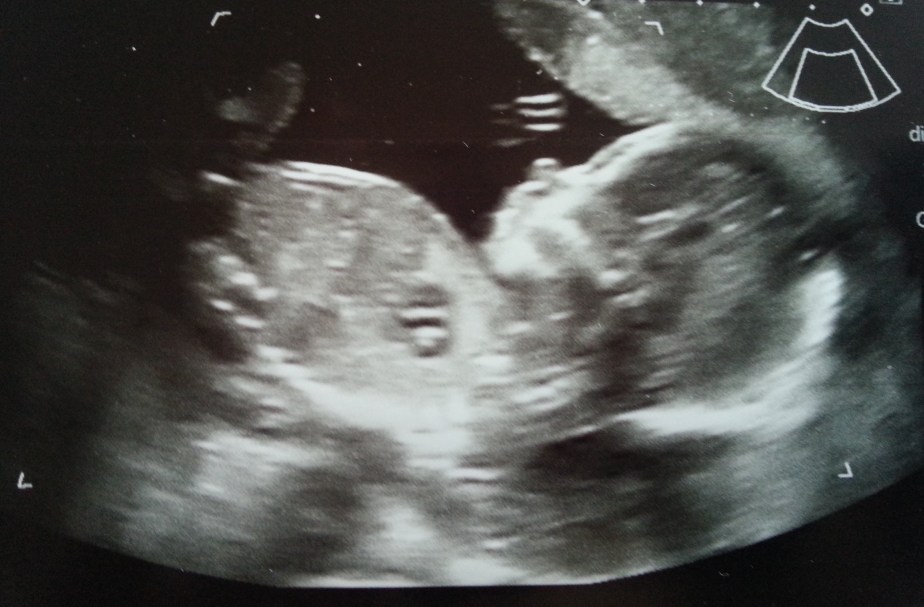

Kūrybinis gyvybės impulsas yra pati galingiausia jėga visatoje. Paslaptingas ir nepaaiškinamas, jis yra reikšmingesnis už materiją, apčiuopiamas sunkiau nei mintis ir tvaresnis už laiką. Nuo žmonijos egzistavimo pradžios mes ieškome paaiškinimo, kaip atsiranda gyvybė. Nors mokslininkai iššifravo genetinį kodą, gyvybė ir toliau lieka didelė paslaptis. Negimęs kūdikis yra sąmoninga, jautri būtybė su savo jausmais, mintimis, prisiminimais. Meilė yra viskas, ko reikia atėjusiai sielai tobulėti. Dauguma mūsų, net neįsivaizduojame, kokį galingą meilės užtaisą turime savo širdyse,manąjį atskleidė Maja.Jis nenuvaldomu greičiu auga, kiekvieną dieną darydamas tobula. Esu labai dėkinga savo nuostabiam vyrui, jis man padovanojo pasaulį – Mają. Ši nuostabi siela, leidžia man pažinti patį jautriausią ir gražiausią jausmą egzistuojantį žemėje – motinystę.